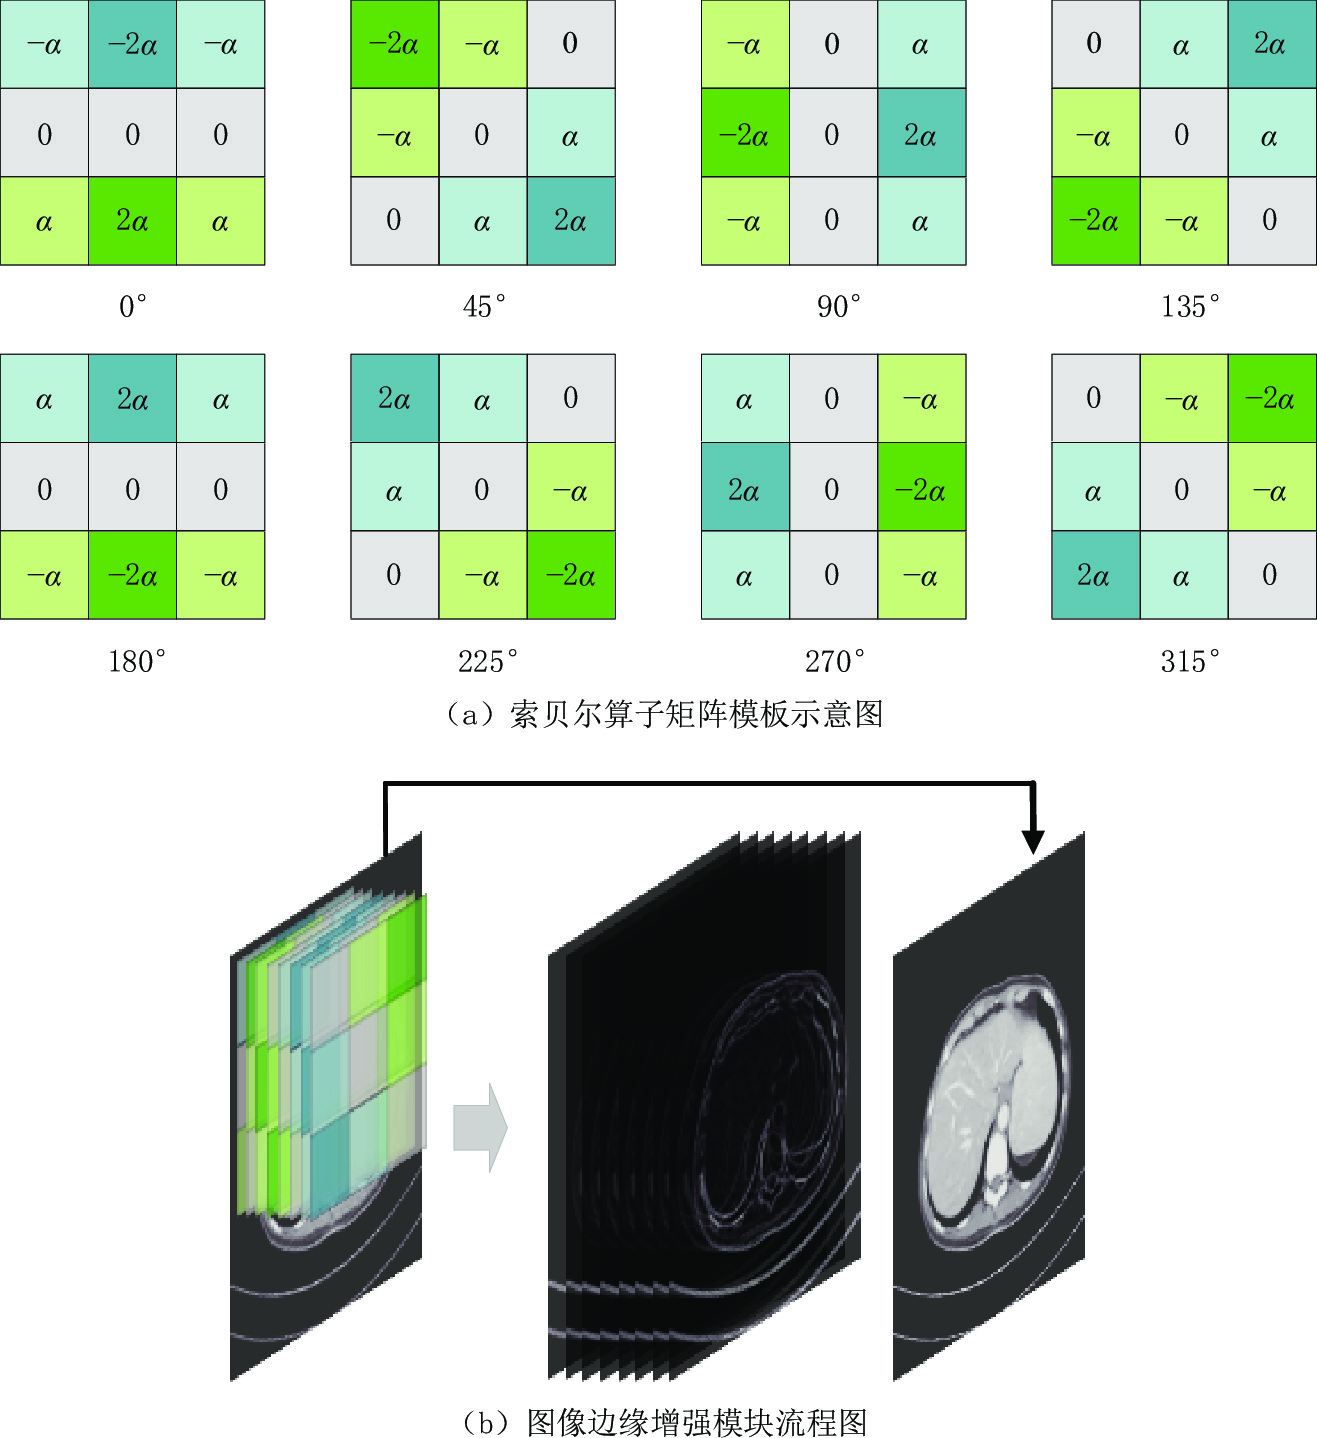

常用于边缘检测的索贝尔算子使用简单、处理速度快且对噪声具有平滑抑制作用,所得图像边缘光滑且连续[24]。为更好的提取图像信息,本文中的图像边缘增强模块利用0°、45°、90°、135°、180°、225°、270°、315° 这8个方向的索贝尔算子矩阵模板(3×3)与对应的图像进行卷积,每个模板对相应方向的边缘影响最大,如图2(a)所示。且该模块中加入可学习参数α,可以在训练过程中进行自适应调整,提取不同强度的细节信息,以更好的适用于肺部、腹部和头部的边缘提取。

具体流程图如图2(b)所示,索贝尔算子的中心与要检测的像素点相对应,进行卷积运算后,得到一组用于提取边缘信息的特征图。该模块将其与输入的低剂量CT图像在通道维度上叠加在一起,得到一幅边缘增强图像。